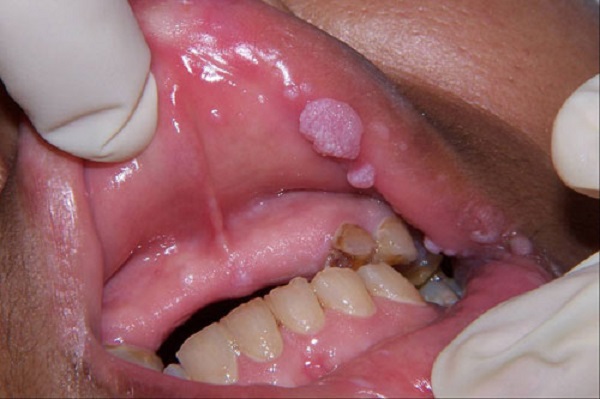

Hình ảnh sùi mào gà ở miệng

– Cũng giống với bệnh sùi mào gà nam giới, sùi mào gà ở nữ giới còn xuất hiện ở miệng, mắt, họng, lưỡi,..

– Ở giai đoạn đầu: Trong giai đoạn đầu tại bộ phận sinh dục và các vùng da lân cận như: Bao quy đầu, thân dương vật, rãnh quy đầu, các nếp gấp bẹn, vùng bìu, lỗ sáo,… Ngoài ra các mụn sùi còn tập trung quanh niêm mạc miệng của bệnh nhân nếu như nó lây truyền qua quan hệ bằng miệng. Bắt đầu xuất hiện các nốt sùi mềm, màu hồng nhạt, mọc đơn lẻ, bề mặt các nốt sùi này ẩm ướt. Các nốt sùi thường không mai những dấu hiệu ngứa ngáy hay khó chịu gì, vì vậy rất khó để phát hiện ra bệnh sùi mào gà ở giai đoạn này.

Hình ảnh sùi mào gà ở nam nữ giới, ở hậu môn hay vùng kín là những vị trí phổ biến và người mắc bệnh có khả năng phát hiện được các biểu hiện của bệnh như: xuất hiện những nốt sần nhỏ nổi li ti ở các vị trí như vùng kín, hậu môn, khoang miệng… Tuy vậy, không ít người bệnh đã bỏ qua các dấu hiệu – triệu chứng bất thường này bởi ban đầu nó khá giống với các nốt mụn, nhiệt miệng hoặc viêm nhiễm thông thường…

Dưới đây là một số hình ảnh sùi mào gà ở nam, nữ giới, ở miệng, vùng kín, hậu môn… mời các bạn cùng tham khảo để có thêm kiến thức giúp dễ dàng nhận biết bệnh sùi mào gà.